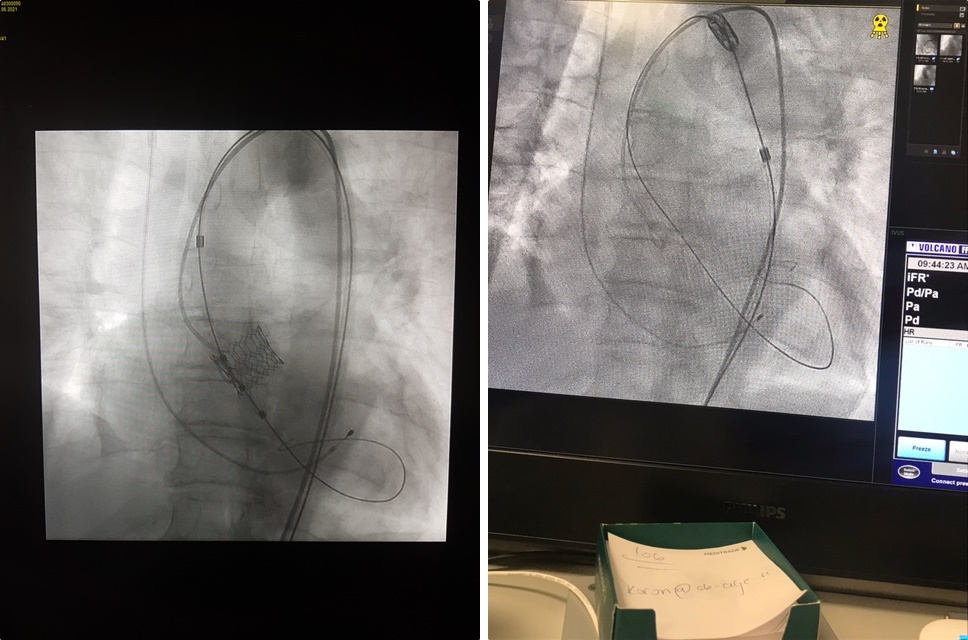

V Splošni bolnišnici Celje so izvedli prva posega vstavitve srčne zaklopke skozi žilo – TAVI (Transcatheter Aortic Valve Implantation). Gre za klinično metodo zdravljenja bolnikov s pomembno zožitvijo aortne zaklopke, ki sta jo do zdaj izvajala le oba klinična centra. Posega sta bila uspešna in pacienta sta tri dni po posegu lahko zapustila bolnišnico.

Perkutana implantacija aortnih zaklopk (TAVI) ali vstavitev srčnih zaklopk skozi žilo na nogi je priznana klinična metoda zdravljenja bolnikov s pomembno zožitvijo aortne zaklopke. Gre za poseg, pri katerem skozi eno od večjih arterij na stegnu uvedejo umetno biološko aortno zaklopko in jo po žilah vodijo do srca in mesta vstavitve. Njena bistvena prednost je minimalna invazivnost posega v telo. Drugi, kirurški načini namreč zahtevajo odprtje prsnega koša, zunajtelesni obtok in dolgotrajno splošno anestezijo. Metoda je bila zato sprva namenjena predvsem bolnikom, pri katerih je klasična operativna zamenjava aortne zaklopke predstavljala preveliko tveganje. Danes se zaradi številnih prednosti malo invazivnega posega, zaradi katerih se bolniki hitro mobilizirajo in rehabilitirajo, TAVI uporablja tudi pri mlajših bolnikih s srednjim tveganjem operativnega posega.

Prva posega je pod mentorstvom prof. dr. Matjaža Bunca, dr. med. iz UKC Ljubljana, prim. dr. Gorazda Koširja, dr. med. in ga. Metke Rebernik Žumer, dipl. med. sestre iz UKC Maribor izvedla ekipa celjskih kardiologov, ki so jo sestavljali dr. Dragan Kovačić, dr. med., Andrej Lipovšek, dr. med., Rafael Skale, dr. med., Boštjan Bercko, dr. med., Ksenija Rovan Krivec, dr. med., Tilen Kerič, dr. med., sestrska ekipa Laboratorija za invazivno srčno diagnostiko ter zdravniška in sestrska ekipa preostalega Kardiološkega oddelka SB Celje. Ob tem so bili v varovanje bolnikov v primeru zapletov vključeni še Oddelek za intenzivno interno medicino pod vodstvom prof. dr. Mateja Podbregarja, dr. med., Oddelek za anesteziologijo, intenzivno medicino operativnih strok in terapijo bolečin pod vodstvom dr. Antona Jošta, dr. med. in Oddelek za žilno kirurgijo pod vodstvom Toma Šiblija, dr. med..